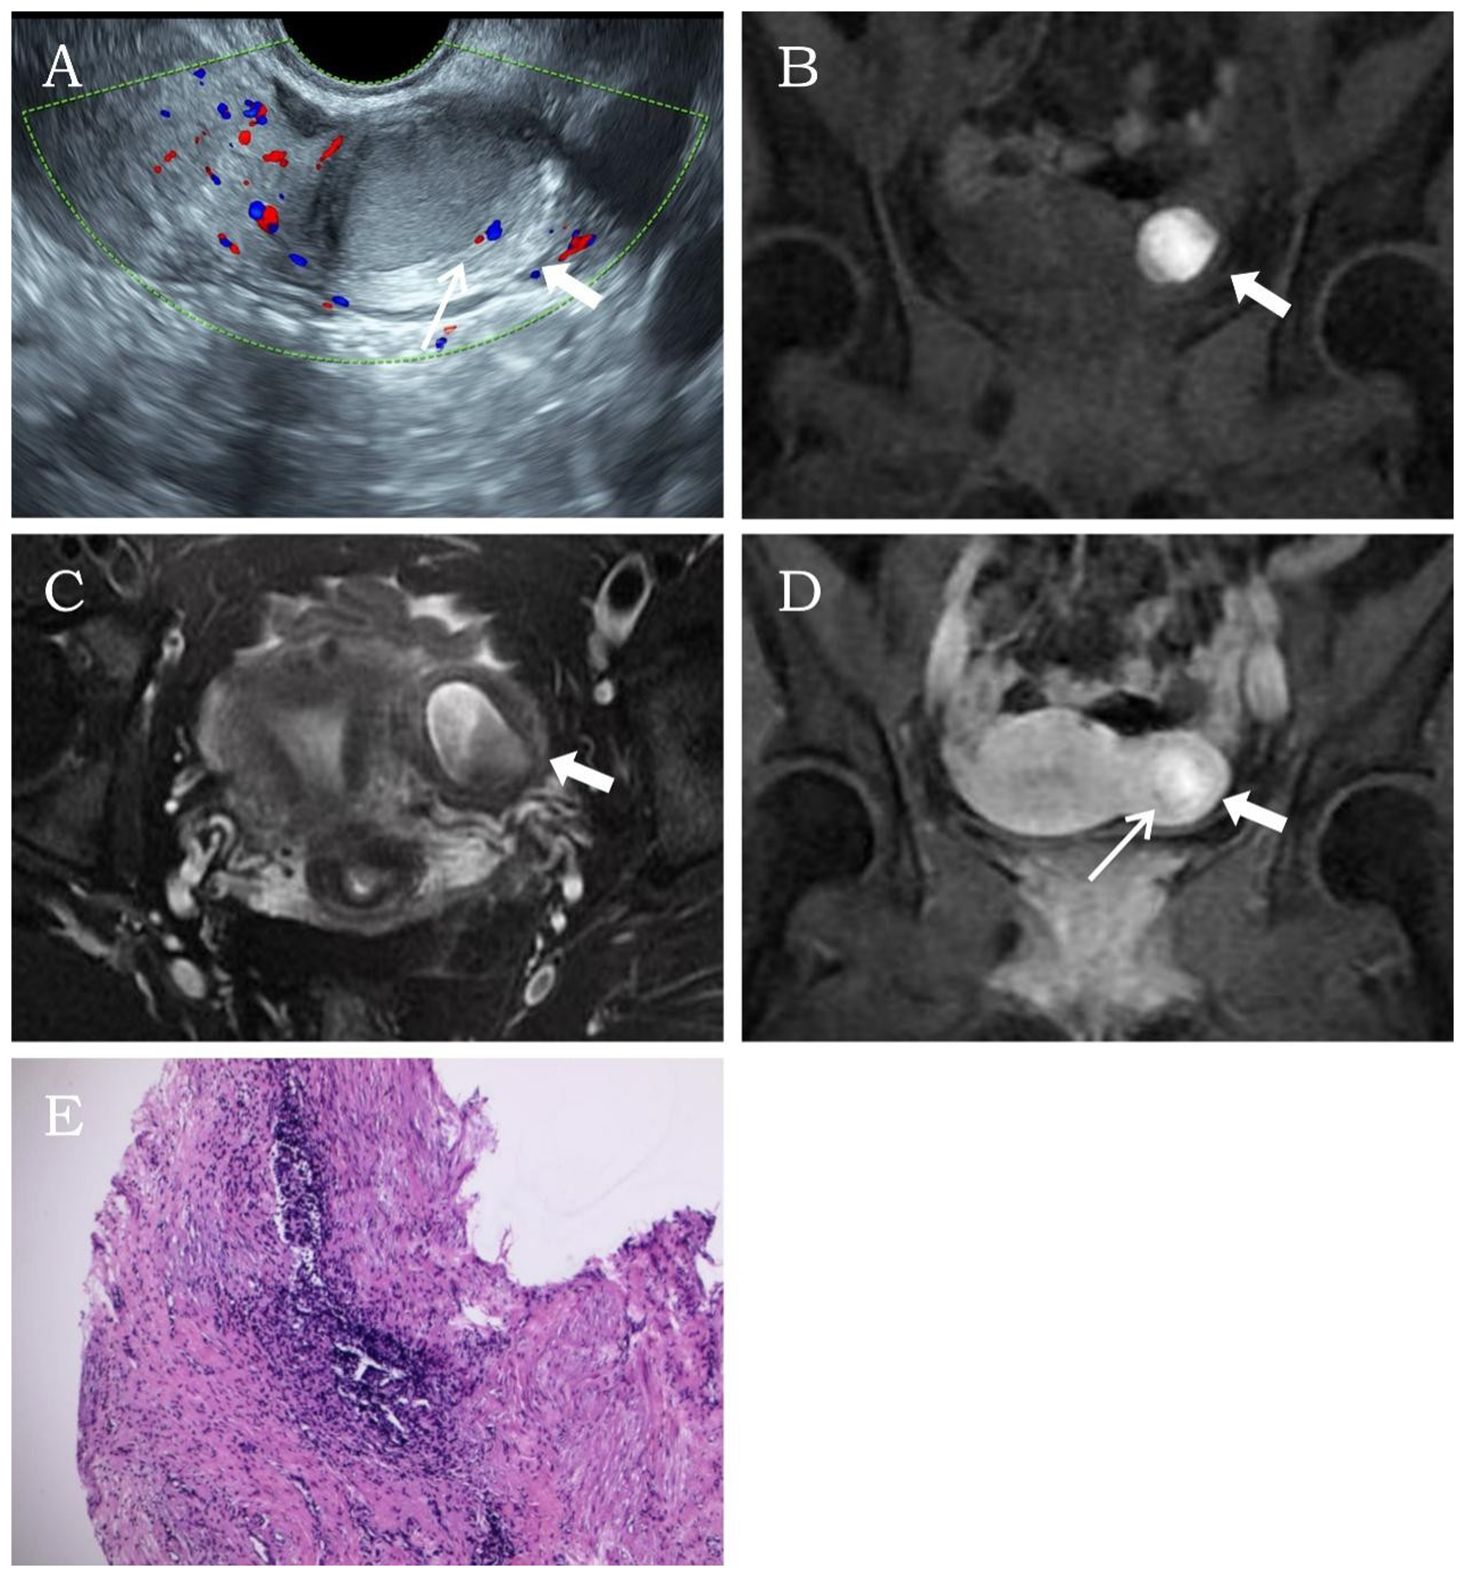

A 26-year-old married nulliparous woman was admitted with a 2-year history of lower abdominal pain. The patient had developed lower abdominal pain 2 years earlier without obvious triggers. The pain occurred either at the end of menstruation or during menstrual onset, lasting variably from 2 to 7 days. It presented as intermittent colicky pain without progressive worsening or other discomfort. Physical examination revealed a moderately firm, minimally mobile, non-tender mass in the left uterine wall. Laboratory tests showed no abnormalities. Transvaginal sonography revealed a well-circumscribed, thick-walled cystic mass (37 × 28 × 34 mm) with regular morphology in the left uterine myometrium, featuring a ground-glass echogenic cavity (15 × 18 × 22 mm) with characteristic endometrial lining (1.2 mm) and a surrounding hypoechoic muscular rim (5.6 mm). The cystic mass showed no communication with the endometrial cavity. No significant abnormalities were detected in the uterine cavity or bilateral adnexal regions. CDFI revealed a circular blood flow signal surrounding the cystic mass (Figure 2A). This finding resulted in a diagnosis of ACUM. The MRI examination demonstrated a round, heterogeneously signal-intense lesion in the left uterine wall, showing high signal intensity on T1WI (Figure 2B) and mixed high-low signal intensity on T2WI (Figure 2C), contrast-enhanced imaging showed no significant central enhancement (Figure 2D), leading to a diagnostic consideration of cystic adenomyosis or rudimentary horn uterus. The patient was diagnosed with ACUM by laparoscopic surgery (Figure 2E) and underwent complete ACUM excision. The patient has remained asymptomatic without recurrence during 24 months of postoperative follow-up.

Figure 2. Representative image of clinical data for the second case. (A) Transvaginal ultrasound reveals a thick-walled cystic mass (thick white arrow) within the left lateral wall of the uterine myometrium. A thin endometrial-like ring (thin white arrow) is observed along the inner wall of the cavity, while the remaining uterine structure appears normal. (B–D) MRI demonstrates an abnormal signal focus (thick white arrow) in the left lateral myometrium, exhibiting heterogeneous internal signals. Post-contrast imaging shows a thin endometrial-like slightly hyperintense signal (thin white arrow) along the inner wall. The T2-weighted image displays a low signal surrounding the inner wall, similar to the myometrium. (E) Histopathological image (H&E, ×10). The submitted smooth muscle tissue is partially lined by endometrium, with scattered endometrial glands and stroma within the muscular wall.